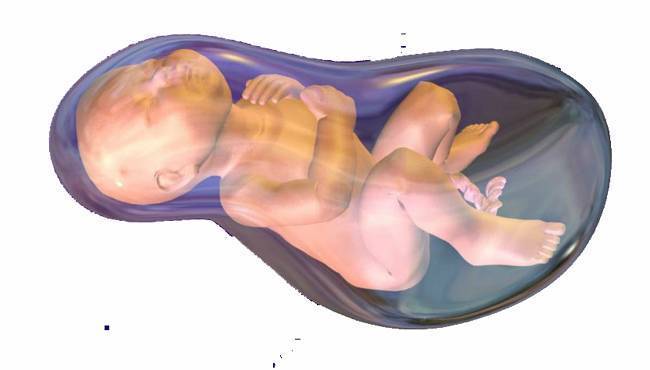

Многоводие при беременности: симптомы и лечение